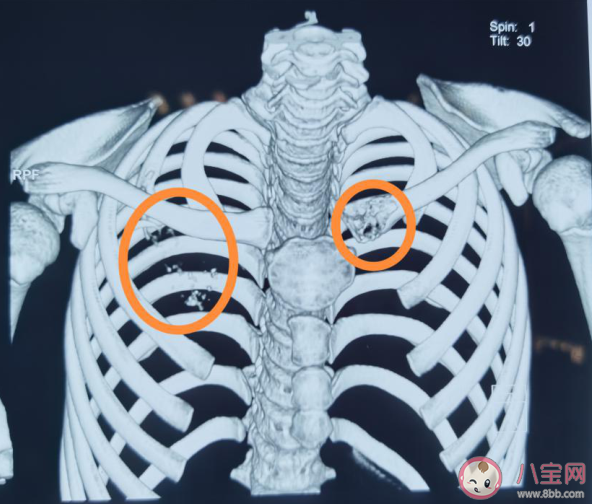

因結(jié)果不同,陳女士立馬帶孩子來(lái)到湖南省腫瘤醫(yī)院就診,最終病理報(bào)告結(jié)果提示:低-未分化鱗癌,結(jié)合所有檢查結(jié)果,醫(yī)院專(zhuān)家目前診斷為原發(fā)性支氣管肺癌,目前肋骨、鎖骨均被癌細(xì)胞啃噬掉一部分,縱隔淋巴結(jié)也發(fā)現(xiàn)轉(zhuǎn)移,考慮肺癌晚期。